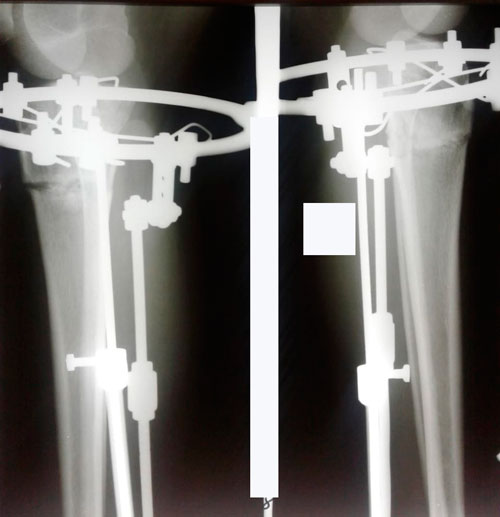

23 день после операции.

Вот в чем суть, щадящей и малотравматичной методики доктора Онипко.

Дата операции 01.06.2018г.

Дата снятия аппаратов 29.08.2018г.

Срок сращения 88 дней.